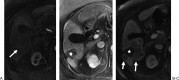

Radiofrequency ablation (RFA) is an alternative therapy for hepatocellular carcinoma and liver metastases when resection cannot be performed or, in the case of hepatocellular carcinoma, when transplant cannot be performed in a timely enough manner to avoid the risk of dropping off the transplant list. RFA has the advantage of being a relatively low-risk minimally invasive procedure used in the treatment of focal liver tumors. This review article discusses the current evidence supporting RFA of liver tumors, as well as the indications, complications, and follow-up algorithms used after RFA.